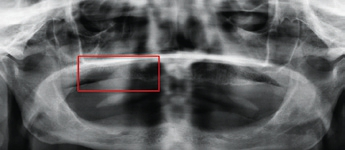

Bei einem 65-jährigen Patienten und Raucher wurde im Juli 2014 ein Plattenepithelkarzinom, T2, N0, diagnostiziert. Die klinische Untersuchung ergab eine ulzerierende, nekrotisierende Läsion im IV. Quadranten mit Verdacht auf knöcherne Infiltration eines Plattenepithelkarzinomrezidivs (Abb. 10 u. 11). Die radiologische Diagnostik legte die Vermutung einer Tumorinfiltration der UK-Kompakta und der Spongiosa nahe (Abb. 12–16). Diagnose: ein invasives, ulzeriertes und mäßig differenziertes Plattenepithelkarzinom, pT4a, G2.